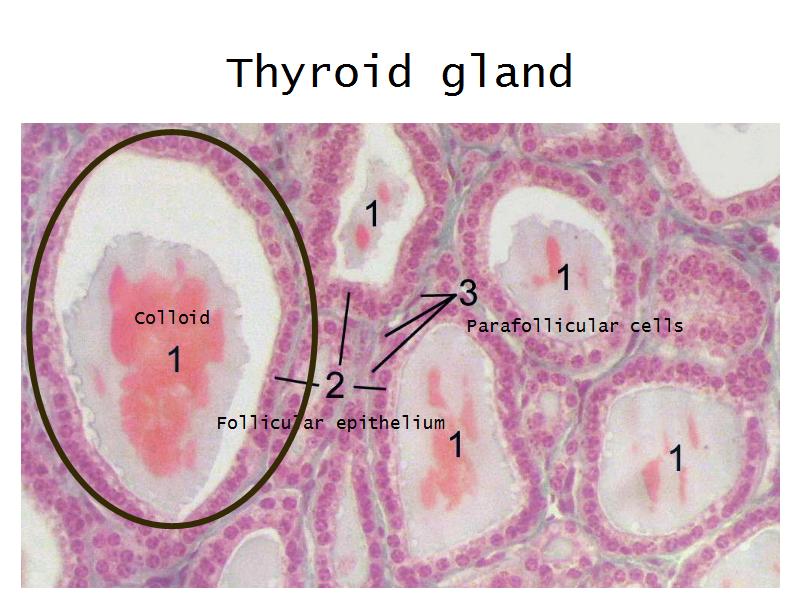

Thyroid gland

Four elements making up the thyroid

Thyroid gland

- Follicle

- Follicular epithelium

- Parafollicular cells

- Colloid

- Identify them on the next slide